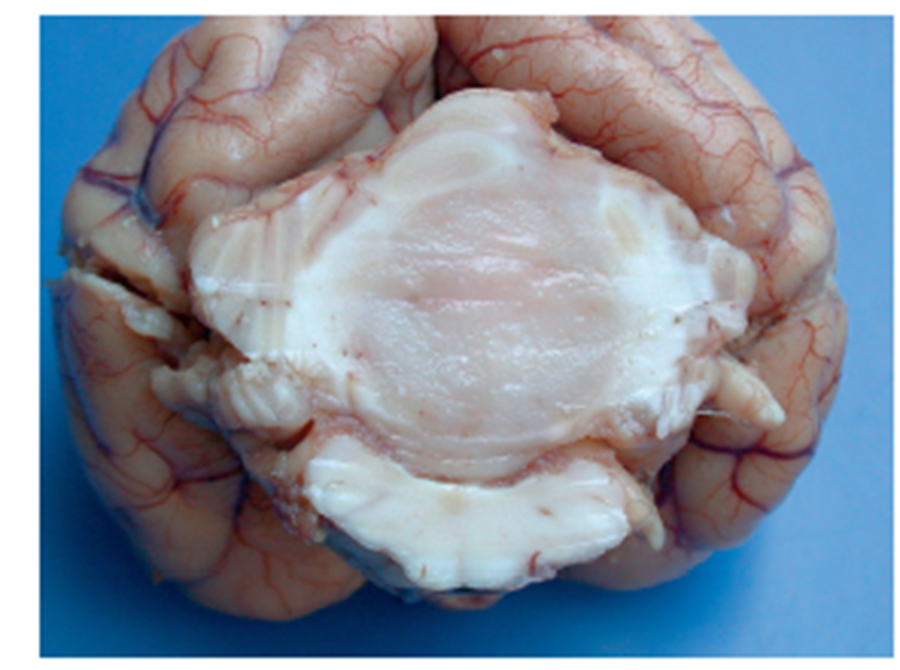

What pathology is shown in this image?

Trigeminal nerve schwannoma